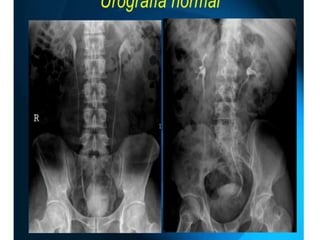

Que es ? Es un tipo de examen que se usa para evaluar los riñones, los uréteres y la vejiga.  también conocida como pielograma intravenoso, se realiza utilizando rayos X convencionales, luego de la administración intravenosa de agentes de contraste radiográficos

Objetivo.  Visualizar panorámicamentelas vías urinarias, evaluando su morfología y función CONTRASTE  Yodado Hidrosoluble